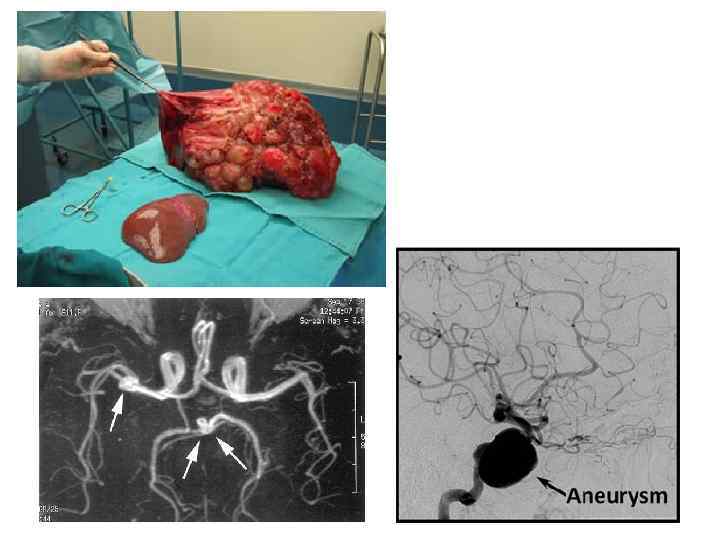

Феохромоцитома • Опухоль, как правило, доброкачественная, состоящая из хромаффинных клеток и продуцирующая катехоламины. • При кризе АД повышается внезапно и в течение нескольких секунд достигает очень высокого уровня (250 -300/150 -130 мм рт. ст. ), сопровождается выраженной тахикардией, бледностью лица, холодным потом, нарушение зрения. Возникает сильная жажда, позывы к мочеиспусканию. В крови — лейкоцитоз и гипергликемия. Кризы могут провоцироваться холодовой пробой, глубокой пальпацией живота, приведением нижних конечностей к животу, приемом допегита, резерпина, клофелина. • В норме приеме 0, 3 мг клофелина уровень катехоламинов в крови (через 2— 3 ч) и суточной моче резко снижается. У больных с опухолью содержание катехоламинов в крови и моче не изменяется. • Повышена экскреция катехоламинов и их метаболитов в суточной моче: адреналина — более 50 мкг, норадреналина — более 100— 150 мкг, ванилилминдальной кислоты (ВМК) — более 6 мкг, в том числе в течение 3 ч после очередного криза.

Феохромоцитома • Опухоль, как правило, доброкачественная, состоящая из хромаффинных клеток и продуцирующая катехоламины. • При кризе АД повышается внезапно и в течение нескольких секунд достигает очень высокого уровня (250 -300/150 -130 мм рт. ст. ), сопровождается выраженной тахикардией, бледностью лица, холодным потом, нарушение зрения. Возникает сильная жажда, позывы к мочеиспусканию. В крови — лейкоцитоз и гипергликемия. Кризы могут провоцироваться холодовой пробой, глубокой пальпацией живота, приведением нижних конечностей к животу, приемом допегита, резерпина, клофелина. • В норме приеме 0, 3 мг клофелина уровень катехоламинов в крови (через 2— 3 ч) и суточной моче резко снижается. У больных с опухолью содержание катехоламинов в крови и моче не изменяется. • Повышена экскреция катехоламинов и их метаболитов в суточной моче: адреналина — более 50 мкг, норадреналина — более 100— 150 мкг, ванилилминдальной кислоты (ВМК) — более 6 мкг, в том числе в течение 3 ч после очередного криза.

Клинические признаки 1. Классическая триада симптомов: сильная головная боль, потливость и сердцебиения. 2. Трудно контролируемая АГ. 3. Необъяснимая синусовая тахикардия. 4. Ортостатическая гипотензия. 5. Возобновляющиеся аритмии. 6. Нейрофиброматоз, пятна "кофе с молоком", болезнь Гиппеля-Ландау, болезнь Штурга. Вебера, туберозный склероз. 7. Осложнения анестезии или хирургических вмешательств в анамнезе. 8. Прессорный ответ на бета-блокаторы. 9. Семейный анамнез феохромоцитомы, медуллярной карциномы щитовидной железы или гиперпаратиреоидизма. Специальные исследования 1. Концентрация метанефринов в моче, их отношение к креатинину мочи. 2. Повышенное содержание катехоламинов (адреналин, норметанефрин), а также допамина в плазме крови в положении лежа на спине в покое не менее чем в течение 20 минут до забора крови. 3. Тест подавления клонидином: отсутствие существенного уменьшения содержания норадреналина и адреналина в плазме крови через 3 ч после приема 0, 3 мг клонидина (тест следует проводить в состоянии покоя у больных, не получающих гипотензивных препаратов). 4. Компьютерная, ЯМР томография или сцинтиграфия с МИБГ.

Клинические признаки 1. Классическая триада симптомов: сильная головная боль, потливость и сердцебиения. 2. Трудно контролируемая АГ. 3. Необъяснимая синусовая тахикардия. 4. Ортостатическая гипотензия. 5. Возобновляющиеся аритмии. 6. Нейрофиброматоз, пятна "кофе с молоком", болезнь Гиппеля-Ландау, болезнь Штурга. Вебера, туберозный склероз. 7. Осложнения анестезии или хирургических вмешательств в анамнезе. 8. Прессорный ответ на бета-блокаторы. 9. Семейный анамнез феохромоцитомы, медуллярной карциномы щитовидной железы или гиперпаратиреоидизма. Специальные исследования 1. Концентрация метанефринов в моче, их отношение к креатинину мочи. 2. Повышенное содержание катехоламинов (адреналин, норметанефрин), а также допамина в плазме крови в положении лежа на спине в покое не менее чем в течение 20 минут до забора крови. 3. Тест подавления клонидином: отсутствие существенного уменьшения содержания норадреналина и адреналина в плазме крови через 3 ч после приема 0, 3 мг клонидина (тест следует проводить в состоянии покоя у больных, не получающих гипотензивных препаратов). 4. Компьютерная, ЯМР томография или сцинтиграфия с МИБГ.